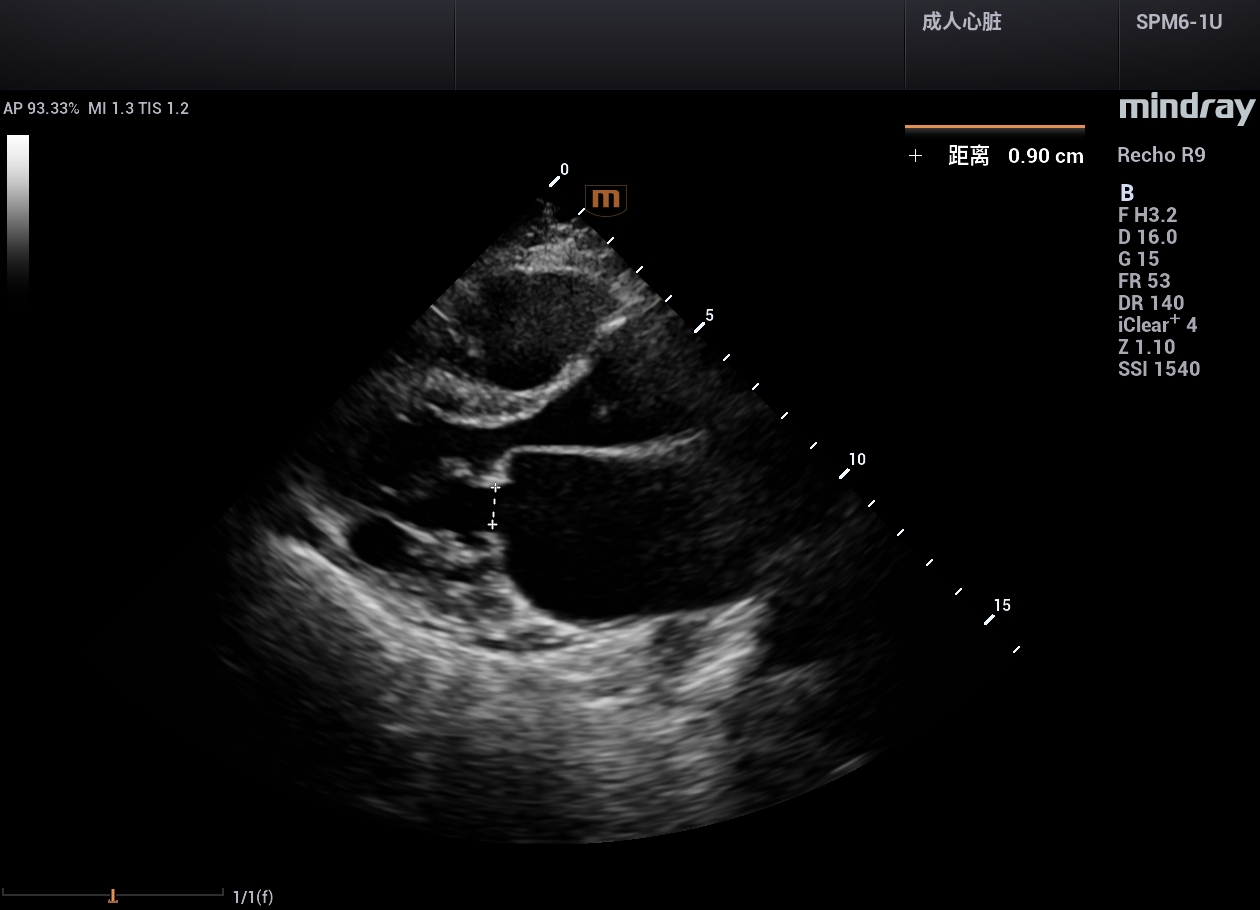

病例,主动脉瓣置换术,有瓣周漏,中山一院广西医院,2024年5月